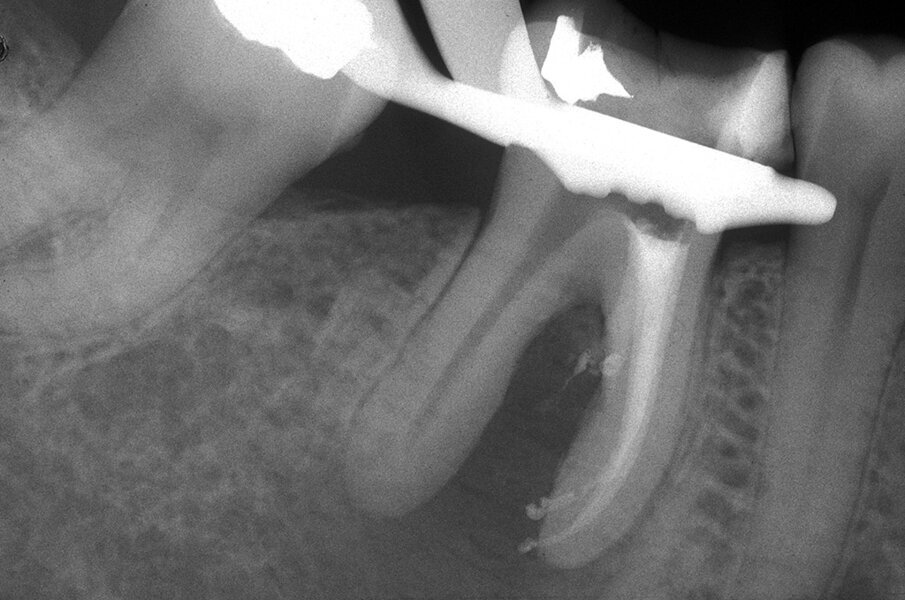

Queste perforazioni possono avvenire nel corso della strumentazione di canali curvi, per l’esecuzione del cosiddetto “trasporto esterno” del forame apicale. Una volta eseguita la perforazione, se l’operatore riesce a ritrovare e preparare il canale originale (con l’utilizzo di strumenti sottili e precurvati, molta irrigazione e soprattutto molta pazienza), il danno provocato dalla perforazione sarà minimo in quanto, soprattutto se la perforazione è piccola, si comporterà come un piccolo canale laterale che sarà facilmente otturato. Se invece il canale originale è rimasto intasato dai detriti di fango dentinale e gli strumenti ogni volta ripercorrono il cammino della perforazione, in tale caso il canale deve essere otturato con le metodiche tradizionali e successivamente l’apice contenente la porzione non trattata del canale radicolare deve essere rimosso per via chirurgica, soprattutto se stiamo trattando un dente necrotico o se siamo di fronte ad un ritrattamento (Figg. 1a-1e).